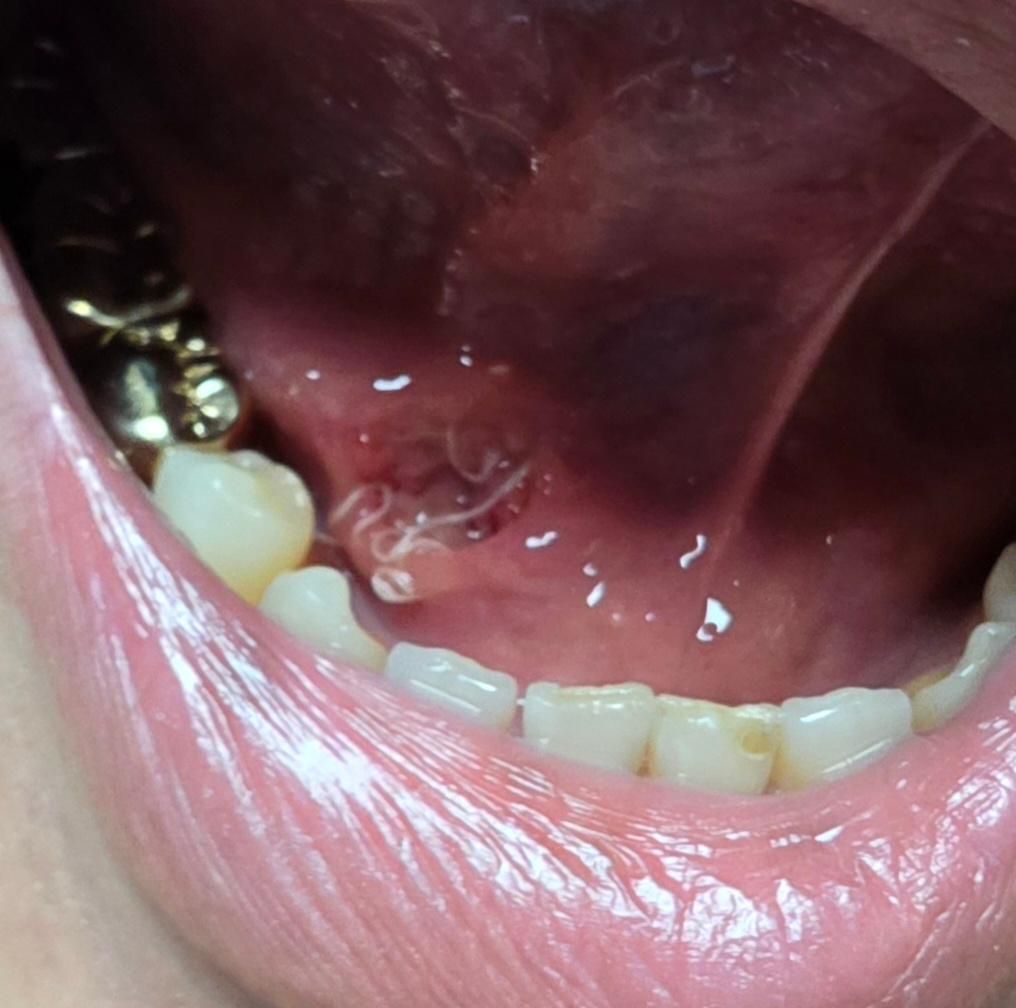

저녁에 죽먹고 약먹고 거울보는데 뭔가 벌어진것같은데 이거 벌어진거 맞나요? 오늘 31일 오전11시 30분에 국소마취로 제거하고 봉합했습니다 입원은 하지않았습니다 녹는실이라고 했는데 뭔가 벌어진것같아요

봉합이 좀 느슨해진 것 같습니다. 아무래도 혀가 계속 움직이다보니 봉합실이 장력을 받아 풀린 것 같네요. 출혈이 있지 않다면 큰 문제는 없을 겁니다.